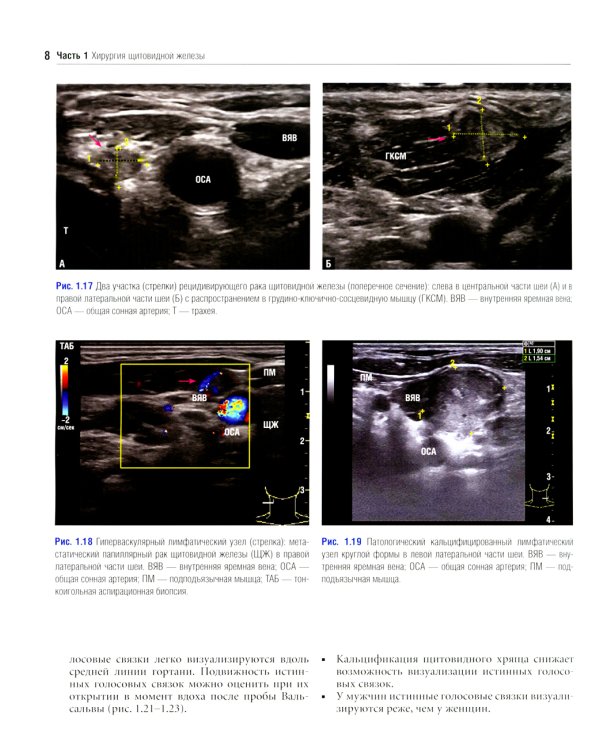

Данное издание представляет собой великолепно иллюстрированный хирургический атлас. В нем рассмотрены методы ультразвукового исследования шеи, молекулярно-генетическое тестирование пациентов с узловыми образованиями в щитовидной железе, робот-ассистированные хирургические методы, техника эндоскопических операций при эндокринных опухолях, хирургия при рецидиве заболевания, аутотранснлантация и криоконсервация околощитовидных желез, адреналэктомия при метастазе в надпочечнике, хирургия нейроэндокринных опухолей тонкой кишки и их метастазов в печени. «Атлас эндокринной хирургии» состоит из 4 частей: «Хирургия щитовидной железы», «Хирургия околощитовидных желез», «Хирургия надпочечников», «Хирургия опухолей поджелудочной железы и карциноидов». Всего в издании 29 глав, подготовленных сотрудниками экспертных факультетов ведущих медицинских школ США, Европы и Азии. Каждая глава состоит из разделов, в которых описаны общие сведения, показания и противопоказания, оценка риска, алгоритм принятия решений и планирование вмешательства, необходимое оборудование и материалы, хирургические техники, результаты лечения, осложнения и последующее наблюдение, а также даны советы и предостережения авторов. В книге много информации, которой нет в других источниках. Наряду с многочисленными фотографиями, сделанными в ходе операций, а также данными, полученными при различных методах визуализации, приведено значительное количество иллюстраций и видеоматериалов, демонстрирующих хирургическую технику или обследование. Издание предназначено практикующим врачам в области эндокринной хирургии, специалистам в смежных областях медицины и студентам медицинских высших учебных заведений.| Издательство | Логосфера |